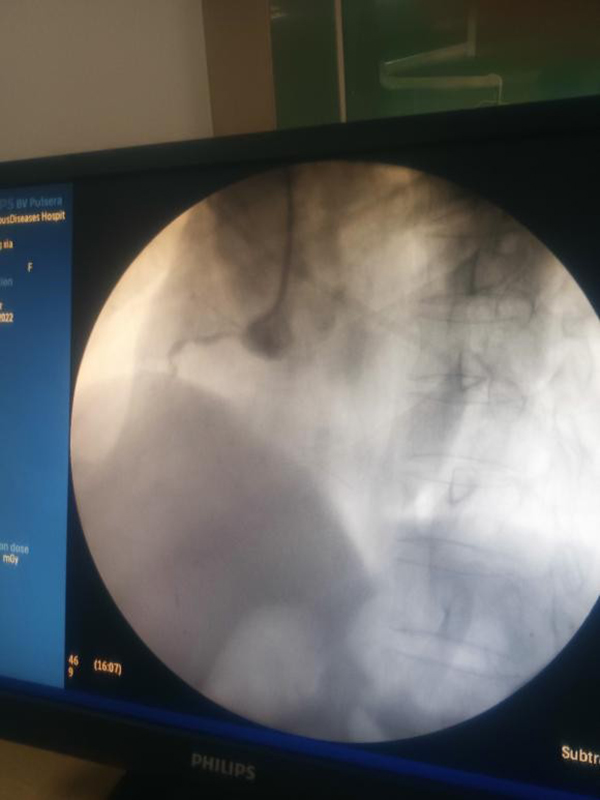

由于市傳染病醫(yī)院沒有DSA手術(shù)機(jī)房,僅有的一臺機(jī)器為非心臟介入手術(shù)所用,沒有心臟血管造影模式,且不能自動(dòng)調(diào)整體位。徐通達(dá)主任與介入導(dǎo)管室技師王文友和護(hù)士李浩積極調(diào)試后,能夠基本滿足冠脈造影需要。同時(shí),積極協(xié)調(diào)徐醫(yī)附院東院盡快準(zhǔn)備手術(shù)所用器械及搶救藥品送至市傳染病醫(yī)院。

按照疫情防控要求,所有參與手術(shù)人員均做好全程防護(hù),嚴(yán)格執(zhí)行防護(hù)措施。這樣給手術(shù)帶來極大的不便。為了做好充分準(zhǔn)備,術(shù)前,徐通達(dá)主任早早將洗手衣、鉛衣、防護(hù)服、面罩、手術(shù)衣穿戴整齊。術(shù)中,徐通達(dá)主任克服了患者耳聾、不?人缘炔荒芎芎门浜弦蛩,以及由于防護(hù)需要防護(hù)鏡產(chǎn)生水汽不能清晰讀圖及造影圖片不清晰等多重困難因素,依靠多年來積累下的經(jīng)驗(yàn),沉著冷靜,嫻熟精準(zhǔn)操作,抽吸血栓,球囊擴(kuò)張,迅速開通患者閉塞的右冠狀動(dòng)脈,植入1枚支架,血流恢復(fù)至TIMI 3級,ST段回落,血壓上升,生命體征逐漸平穩(wěn)。經(jīng)過徐醫(yī)附院醫(yī)護(hù)團(tuán)隊(duì)的共同努力,患者得到成功救治。